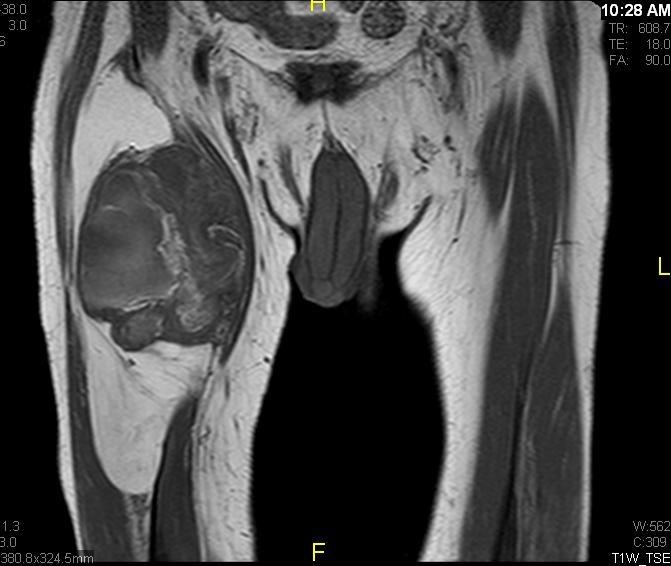

Fig. 1 & 2 Magnetic Resonance Image shows a large heterogeneous mass in the left gluteal region with low intensity signal on Axial (Fig. 1) and Coronal (Fig. 2) T1-weighted images admixed with some high signal areas indicative of fatty tissue. Higher intensity signal is visible compatible with hemorrhage or necrotic tissue. The mass involve the central portion of the left iliac bone.

Axial (Fig. 4) and Coronal (Fig. 5) contrasted T1-weighted MR images show a large heterogeneous mass with central and peripheral enhancement. Central low signal intensity image is compatible with necrosis and hemorrhage.

Fig. 7 & 8 Magnetic Resonance Image shows a large heterogeneous mass in the right thigh with low intensity signal on Axial (Fig. 7) and Coronal (Fig. 8) T1-weighted images admixed with high signal areas. The high signal areas represent low grade fatty tissue and low signal the dedifferentiated areas. Higher intensity signal is visible compatible with hemorrhage or necrotic tissue.